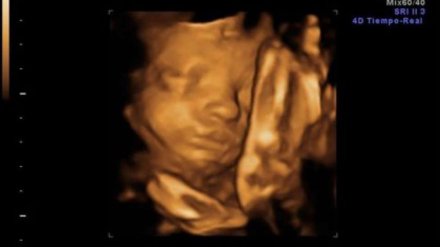

"El latido del corazón, la señal de la VIDA"

La Asamblea de la Vida y NEOS apoyan las medidas propuestas por el gobierno de Castilla y León, a favor de la vida y en contra de una cultura y de una política de la muerte